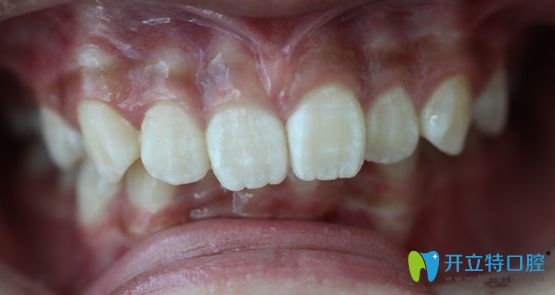

標(biāo)準(zhǔn)的牙齒咬合圖片

<標(biāo)準(zhǔn)的牙齒咬合圖片~>

如圖所示,這才是正常的咬合和牙齒排列位置嘛。不過(guò),這兩張圖的主人可是同一人哦!想必大家也猜到了吧,是的,這就是小A經(jīng)歷兩年矯正生涯后的成果。

這前后差異也太大了吧,難怪那么多人都說(shuō)“整牙堪比整容”。是該感嘆口腔醫(yī)學(xué)的發(fā)達(dá)呢,還是這位醫(yī)生的技術(shù)太贊呢,應(yīng)該兩者兼?zhèn)浒桑?/p>

深覆合深覆蓋矯正好了的效果圖

<深覆合深覆蓋矯正好了!>